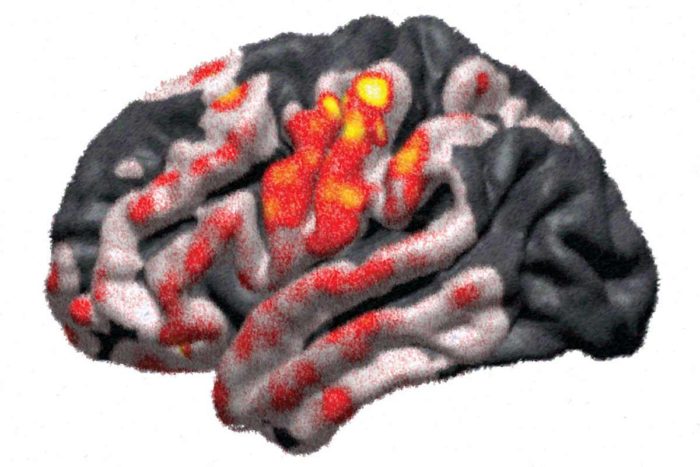

Both sides of the brain are active during one-sided arm movement